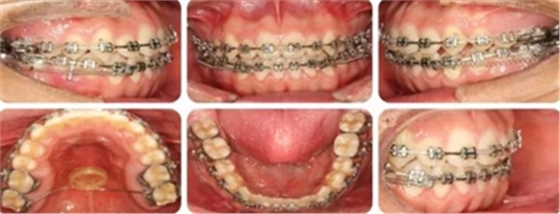

14個月,前牙開頜得到改善,配合使用垂直牽引。

16個月,前牙開頜糾正。

結(jié)束時,可見前牙覆合覆蓋正常,上下牙列排齊,雙側(cè)尖磨牙達到中性關(guān)系。